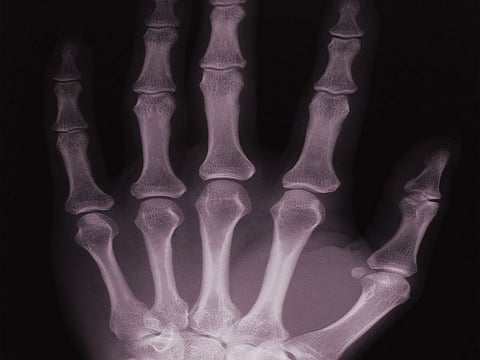

Para estudiar el fenómeno, los radiólogos pidieron a 40 personas, de 18 a 63 años de edad, que estiraran sus dedos un total de 400 veces. Los participantes eran 30 individuos que tronaban los nudillos de forma habitual y 10 que normalmente no tronaban los nudillos.

Unos expertos ortopédicos examinaron las manos de los participantes y observaron que el tronido de los nudillos no provocó ningún daño aparente.

"No encontramos ninguna hinchazón o ninguna pérdida en la fuerza del agarre en las personas que tronaban sus nudillos con respecto a las que nunca lo habían hecho", señaló Boutin.